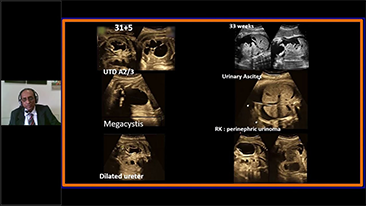

Technologia